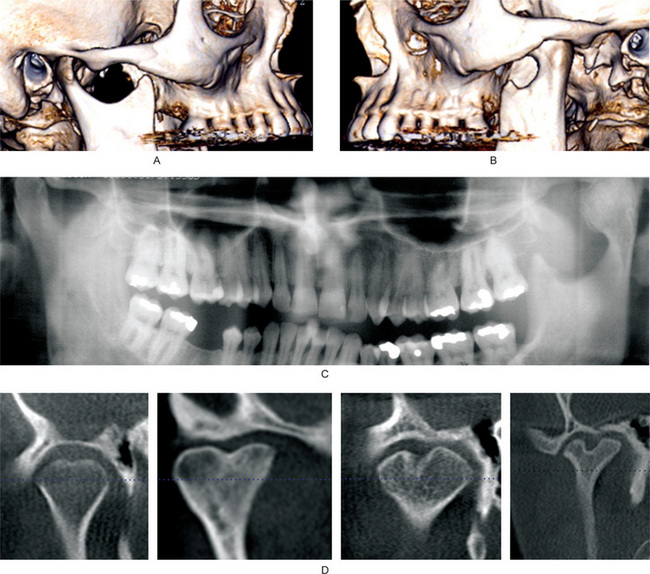

Degenerative joint disease is diagnosed radiographically. CBCT and CT are the reliable examinations to diagnose degenerative changes (Fig. 17-44). MRI and panoramic radiographs have limited value in diagnosing early degenerative changes. Ahmad et al, have described the diagnostic criteria for degenerative joint disease. Radiographically, a joint is considered osteoarthritic if it fulfils any of the following criteria: (i) the condyle has osteophytes, (ii) condyles or fossa/eminence has subcortical erosion or (iii) condyles or fossa/eminence has subcortical pseudocysts. An osteophyte is defined as a marginal hypertrophy with sclerotic borders and exophytic angular formation of osseous tissue arising from the surface of the condyle. Subcortical erosion is defined as loss of continuity of articular cortex. A subcortical pseudocyst is defined as a cavity below the articular surface that deviates from normal marrow pattern.

Figure 17-44 Computed tomographic findings of normal and osteoarthritic temporomandibular joints.

(A) Sagittal view of a normal temporomandibular joint, which has smooth, rounded and well-defined cortical margin of the condyle and the fossa. (B) Axially corrected coronal view of a normal temporomandibular joint which has smooth, rounded and well-defined cortical margins. (C) Sagittal view of a temporomandibular joint that shows signs of remodeling. Anterior slope of the condylar head is flat. (D) An axially corrected coronal view showing remodeling of the condylar head. The lateral slope of the condylar head is flat. (E–J) Images of joints with degenerative joint disease. (E, F) Sagittal views showing erosion of the condylar heads. The continuity of the cortical margin is lost. (G) A condyle with generalized sclerosis, osteophyte at the anterior margin, and several subcortical pseudocysts (arrows). (H–J) From cone beam computed tomography. (H) An osteophyte at the anterior margin of the condylar head and a subcortical pseudocyst (arrow). (I) A prominent osteophyte, which often appears as a bird’s beak. (J) A prominent anterior osteophyte, sclerosis of the superior part of the condylar head, and flattening of the articular eminence.

Rheumatoid arthritis, in its early stages, may be manifested by slight fever, loss of weight and fatigability. The joints affected are swollen, and the patient complains of pain and stiffness. Involvement of the TMJ may occur concomitantly with the other joint lesions or may arise at any subsequent time. Radiographically, joints may be irregular (Fig. 17-45). Articular surfaces become flat. Subcortical pseudocysts and osteophytes may be present.

Figure 17-45 Cone beam computed tomography of a patient with bilateral involvement with rheumatoid arthritis.

(A) Sagittal view of the right joint. Superior margin of the condylar head is irregular. (B) An axially corrected coronal view of the right joint, which shows inter-digitation of bony projections that lead to ankylosis of the joint. A subcortical pseudocyst (arrow) is present in the condylar head. (C) A reconstructed panoramic radiograph from the cone beam scan. The dentition appears within normal limits, with the exception of congenitally missing mandibular left second premolar. (D, E) Sagittal and coronal sections of the left joint. Superior margin of the left condylar head is irregularly flat and has prominent notching. The articular fossa is also flat.